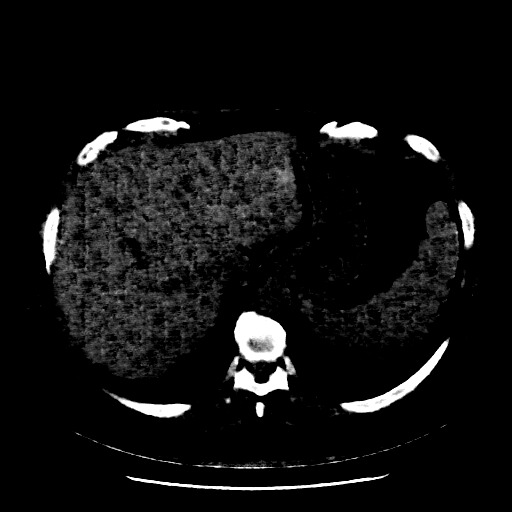

Image Grid

4×3 grid: Rows show different image types (Original NATIVE, Reconstructed NATIVE, Original VENOUS, Generated VENOUS), Columns show windowing techniques (No Window, Lung Window, Mediastinum Window)

Reconstructed NATIVE CT scan (cycle consistency)

Mediastinum window (WL 40, WW 400 → Low −160, High +240)

Actual HU range: [-160.0, 240.0]

Original VENOUS CT scan

Mediastinum window (WL 40, WW 400 → Low −160, High +240)

Actual HU range: [-160.0, 240.0]

Generated VENOUS CT scan (A→B translation)

Mediastinum window (WL 40, WW 400 → Low −160, High +240)

Actual HU range: [-160.0, 240.0]